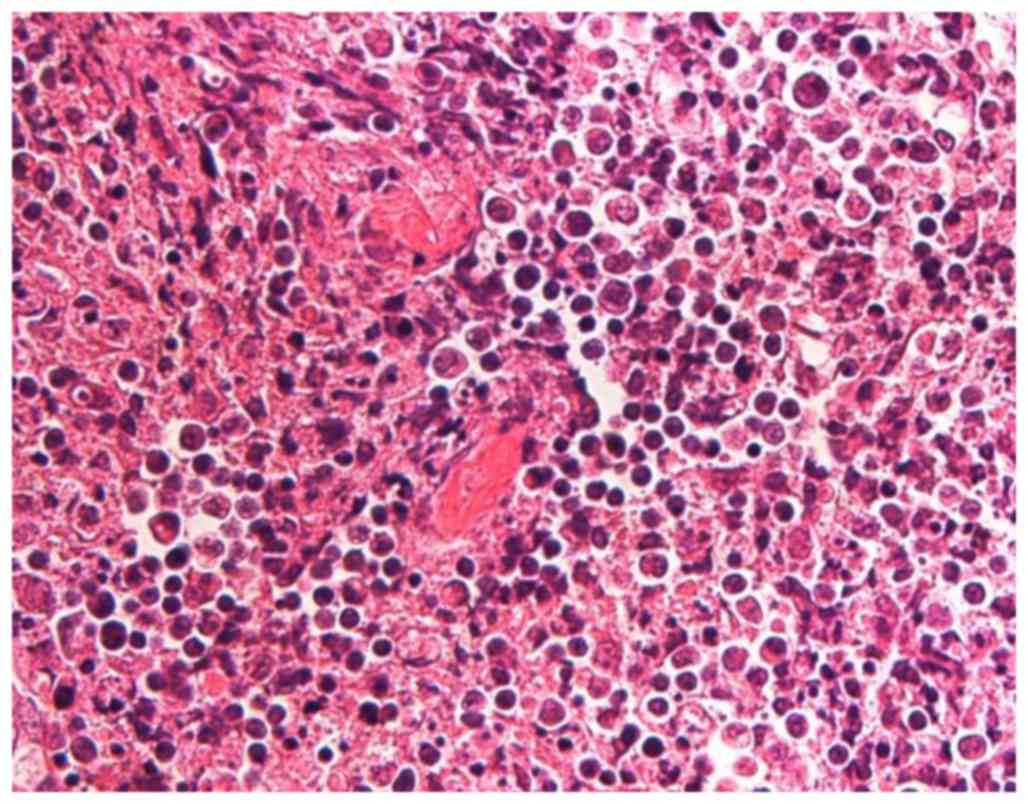

Kikuchi-Fujimoto disease in the regional lymph nodes with node metastasis in a patient with tongue cancer: A case report and literature review

Kikuchi-Fujimoto disease (KFD), also known as histiocytic necrotizing lymphadenitis, is a rare self‑limiting disorder typically affecting the cervical lymph nodes (LNs), which is often misdiagnosed as other LN‑associated diseases. KFD frequently presents with necrotic lesions and recurrences, which are also features of metastatic LNs. Clinicians may thus suspect LN metastasis when they encounter ipsilateral cervical lymphadenopathy in a patient with head and neck cancer. The present study reports the case of a 48‑year‑old man with tongue cancer and KFD affecting the right edge of his tongue and ipsilateral cervical LNs. LN metastasis was initially suspected, but pathological examination of the dissected LNs revealed one necrotic metastatic lesion and two necrotic KFD lesions. Ipsilateral cervical lymphadenopathy recurred 6 years after the initial surgery, and it was not possible to differentiate clinically between a second primary tumor and recurrent KFD prior to treatment. To the best of our knowledge, this is the first reported case of simultaneous tongue cancer, regional LN metastasis and KFD. This highlights the requirement to consider KFD in the event of LNs with necrotic lesions but no cancerous cells. A combination of clinical and pathological approaches may aid in the diagnosis of KFD, in addition to ruling out LN metastasis in initial and recurrent lymphadenopathies. The present study indicate that a diagnosis of KFD should be considered in patients with head and neck cancer that exhibit necrotic LNs lacking cancerous cells. This is important, as misdiagnosis of KFD as LN metastasis may lead to unnecessary adjuvant therapy.